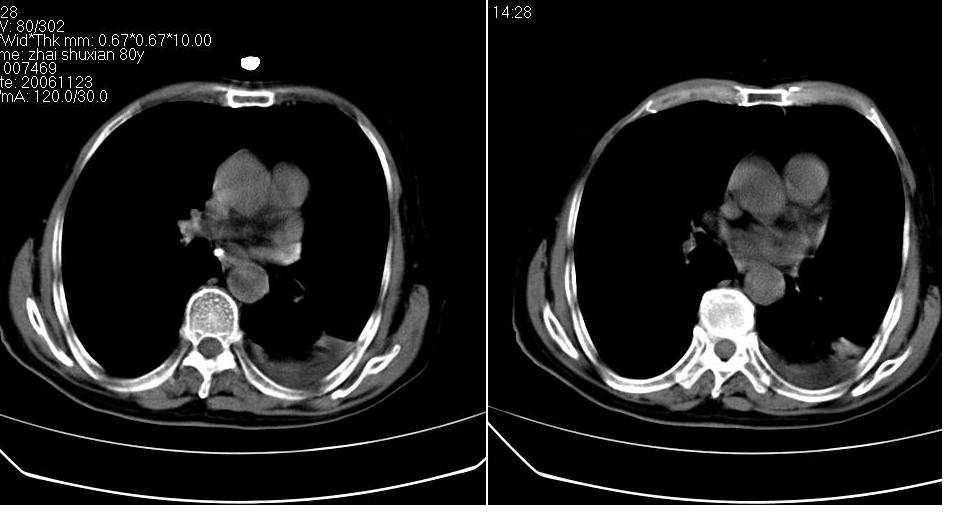

男 80岁,外院病人,有脑梗塞病史,近两个月发热,体温38.5度左右,抗炎后体温正常,药物停有发热。

左肺下叶略萎陷、实变,内可见含气支气管征。左舌叶、中叶亦见少许斑片状高密度区,边界不清。纵隔未见肿大淋巴结影。

左下肺体积缩小,密度增高,见片增密影。边界模糊,见支气管充气像,肺门纵隔无异示,心脏气管左移,左侧胸腔少量积液。考虑肺部感染伴部分肺不张[有脑梗塞病史坠积性肺炎可能]

左肺下叶体积缩小,成类楔形软组织影,其内可见部分含气支气管影,相应左侧肺门区未见明显肿块,考虑炎性病变,建议抗炎后短期复查

左下肺体积缩小,密度增高,并见大片状致密影,边界模糊,其内见支气管充气像,肺门纵隔无异常,心脏气管左移,左侧胸腔少量积液。考虑:左肺炎性病变伴不张。